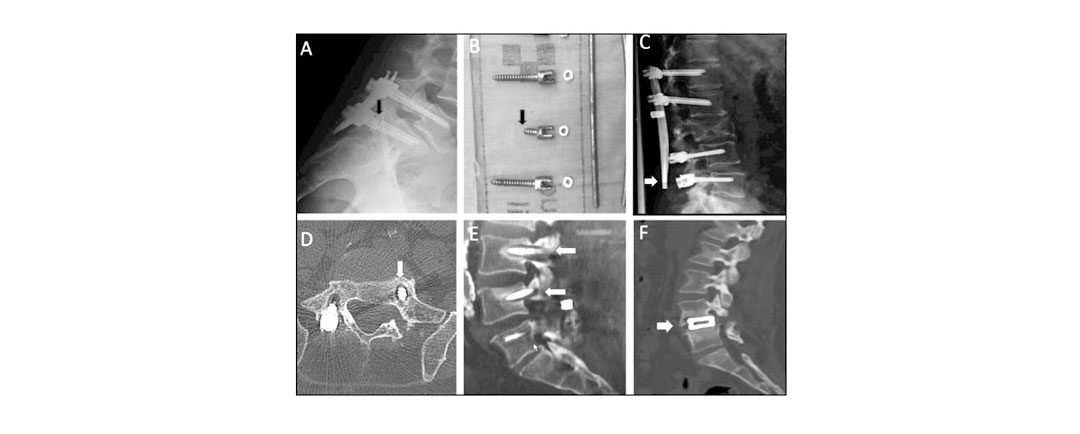

Se hace Artrodesis vertebral posterior cuando: Pasos de la Artrodesis vertebral posterior: La columna vertebral está compuesta por vértebras que están separadas por tejidos blandos que actúan como cojines y mantienen su posición. Lesiones musculoesqueléticas pueden...